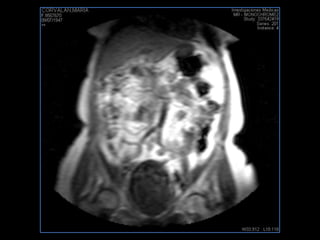

PROTOCOLO pelvis SAG T2, Y FAT SAT (FINOS) AXIAL T1  AX FAT SAT CON   GADOLINIO :  AX T1 Y COR T1 SAT: NO  FASE: RL THK: 3MM  COIL:  GAP: (FACTOR 1.4) 1MM FOV: 40 CM NEX:2 SINCRONIZACION RESPIRATORIA EN 3 O 4 CICLOS ALE

resonancia de abdomen